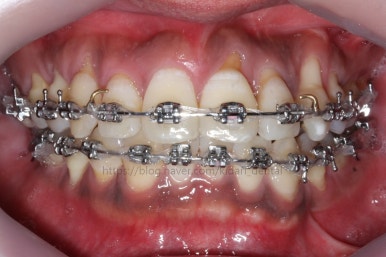

부산치아교정 키다리아저씨치과에 처음 내원 당시의 입안 모습입니다.

여러 가지 문제점이 있는데 하나씩 살펴볼게요.

치열이 많이 삐뚤하네요.

많이 삐뚠 상태에서 장기간 사용하다 보면 안좋은 방향으로 치아가 힘을 받게 되고 마모나 치아 목부분 패임이 심해집니다.

양치가 힘들어요. 양치가 힘들다 보니 세게 닦게 되고 치아 손상은 더 심해져요. 25세의 나이였는데 나이에 비해서 치아나이가 굉장히 많은거죠.